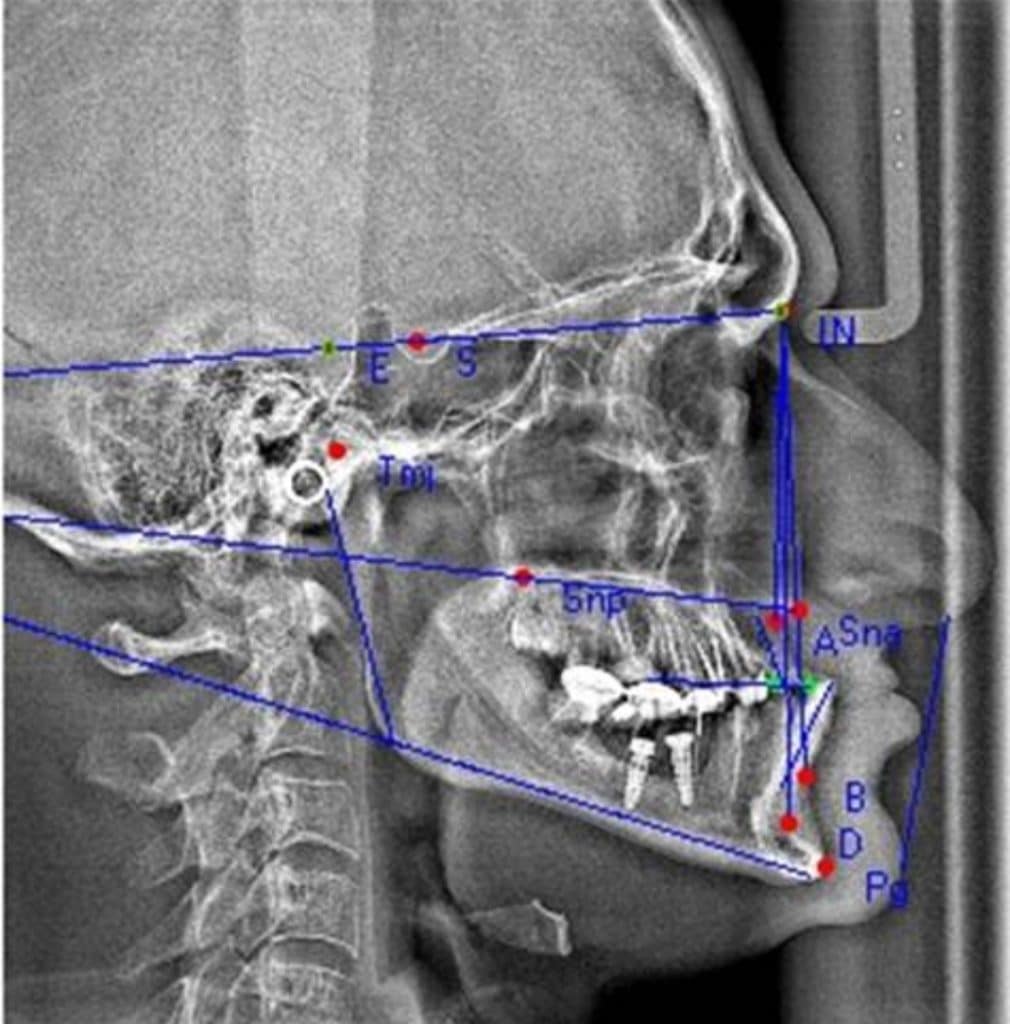

The patient was normally class I occlusion type ( according to old photos and cephalometric analysis) till he received this defective restorations 10 years ago

With time, the mandible shifted till become habitual class III

The patient was diagnosed by orthodontist, oral surgeon and prosthodontist to make the best treatment plan